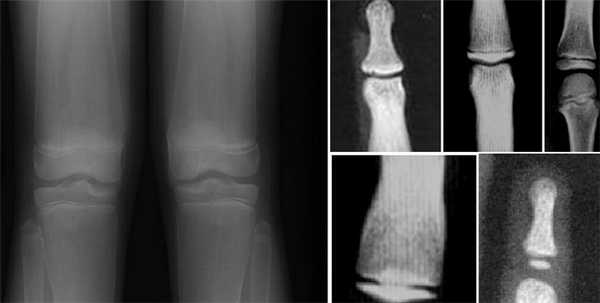

Рентгенологически выявляется симметричное булавовидное вздутие метафизов и частично диафизов длинных трубчатых костей; корковое вещество в этих местах резко истончено. Наиболее выраженные изменения бывают в бедренных и берцовых костях, вблизи коленных суставов, в грудинных концах ключиц и ребрах. На рентгенограмме черепа, как правило, выражен гиперостоз костей свода черепа и челюстей, отмечается отсутствие воздуха в околоносовых полостях, заполненных костными разрастаниями.

Минимальные диагностические признаки: булавовидное расширение метафизов длинных трубчатых костей, выявляемое рентгенологически.

Рентгенологически выявляются булавовидное вздутие метафизов длинных и коротких трубчатых костей, медиальных половин ключиц и передних концов ребер, расширение лонных и седалищных костей, умеренная платиспондилия, умеренная супраорбитальная гиперплазия. Популяционная частота неизвестна.